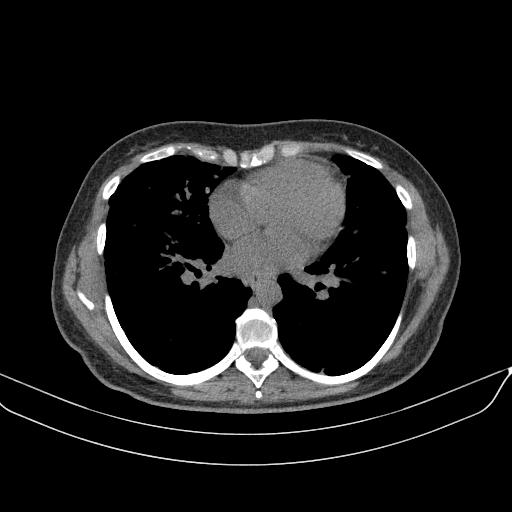

Targeted Slice 70 - Mediastinum Window Analysis (Generated vs Real Venous)

0.762

Mediastinum SSIM

47.9

Mediastinum RMSE

17.1

Mediastinum MAE

Average Mediastinum Window Metrics Across All Slices (133 slices) - Generated vs Real Venous

0.740

Mediastinum SSIM (Avg)

46.9

Mediastinum RMSE (Avg)

17.0

Mediastinum MAE (Avg)

Original VENOUS CT scan

No window - Raw intensity values

Mediastinum window (WL 40, WW 400 β†’ Low βˆ’160, High +240)